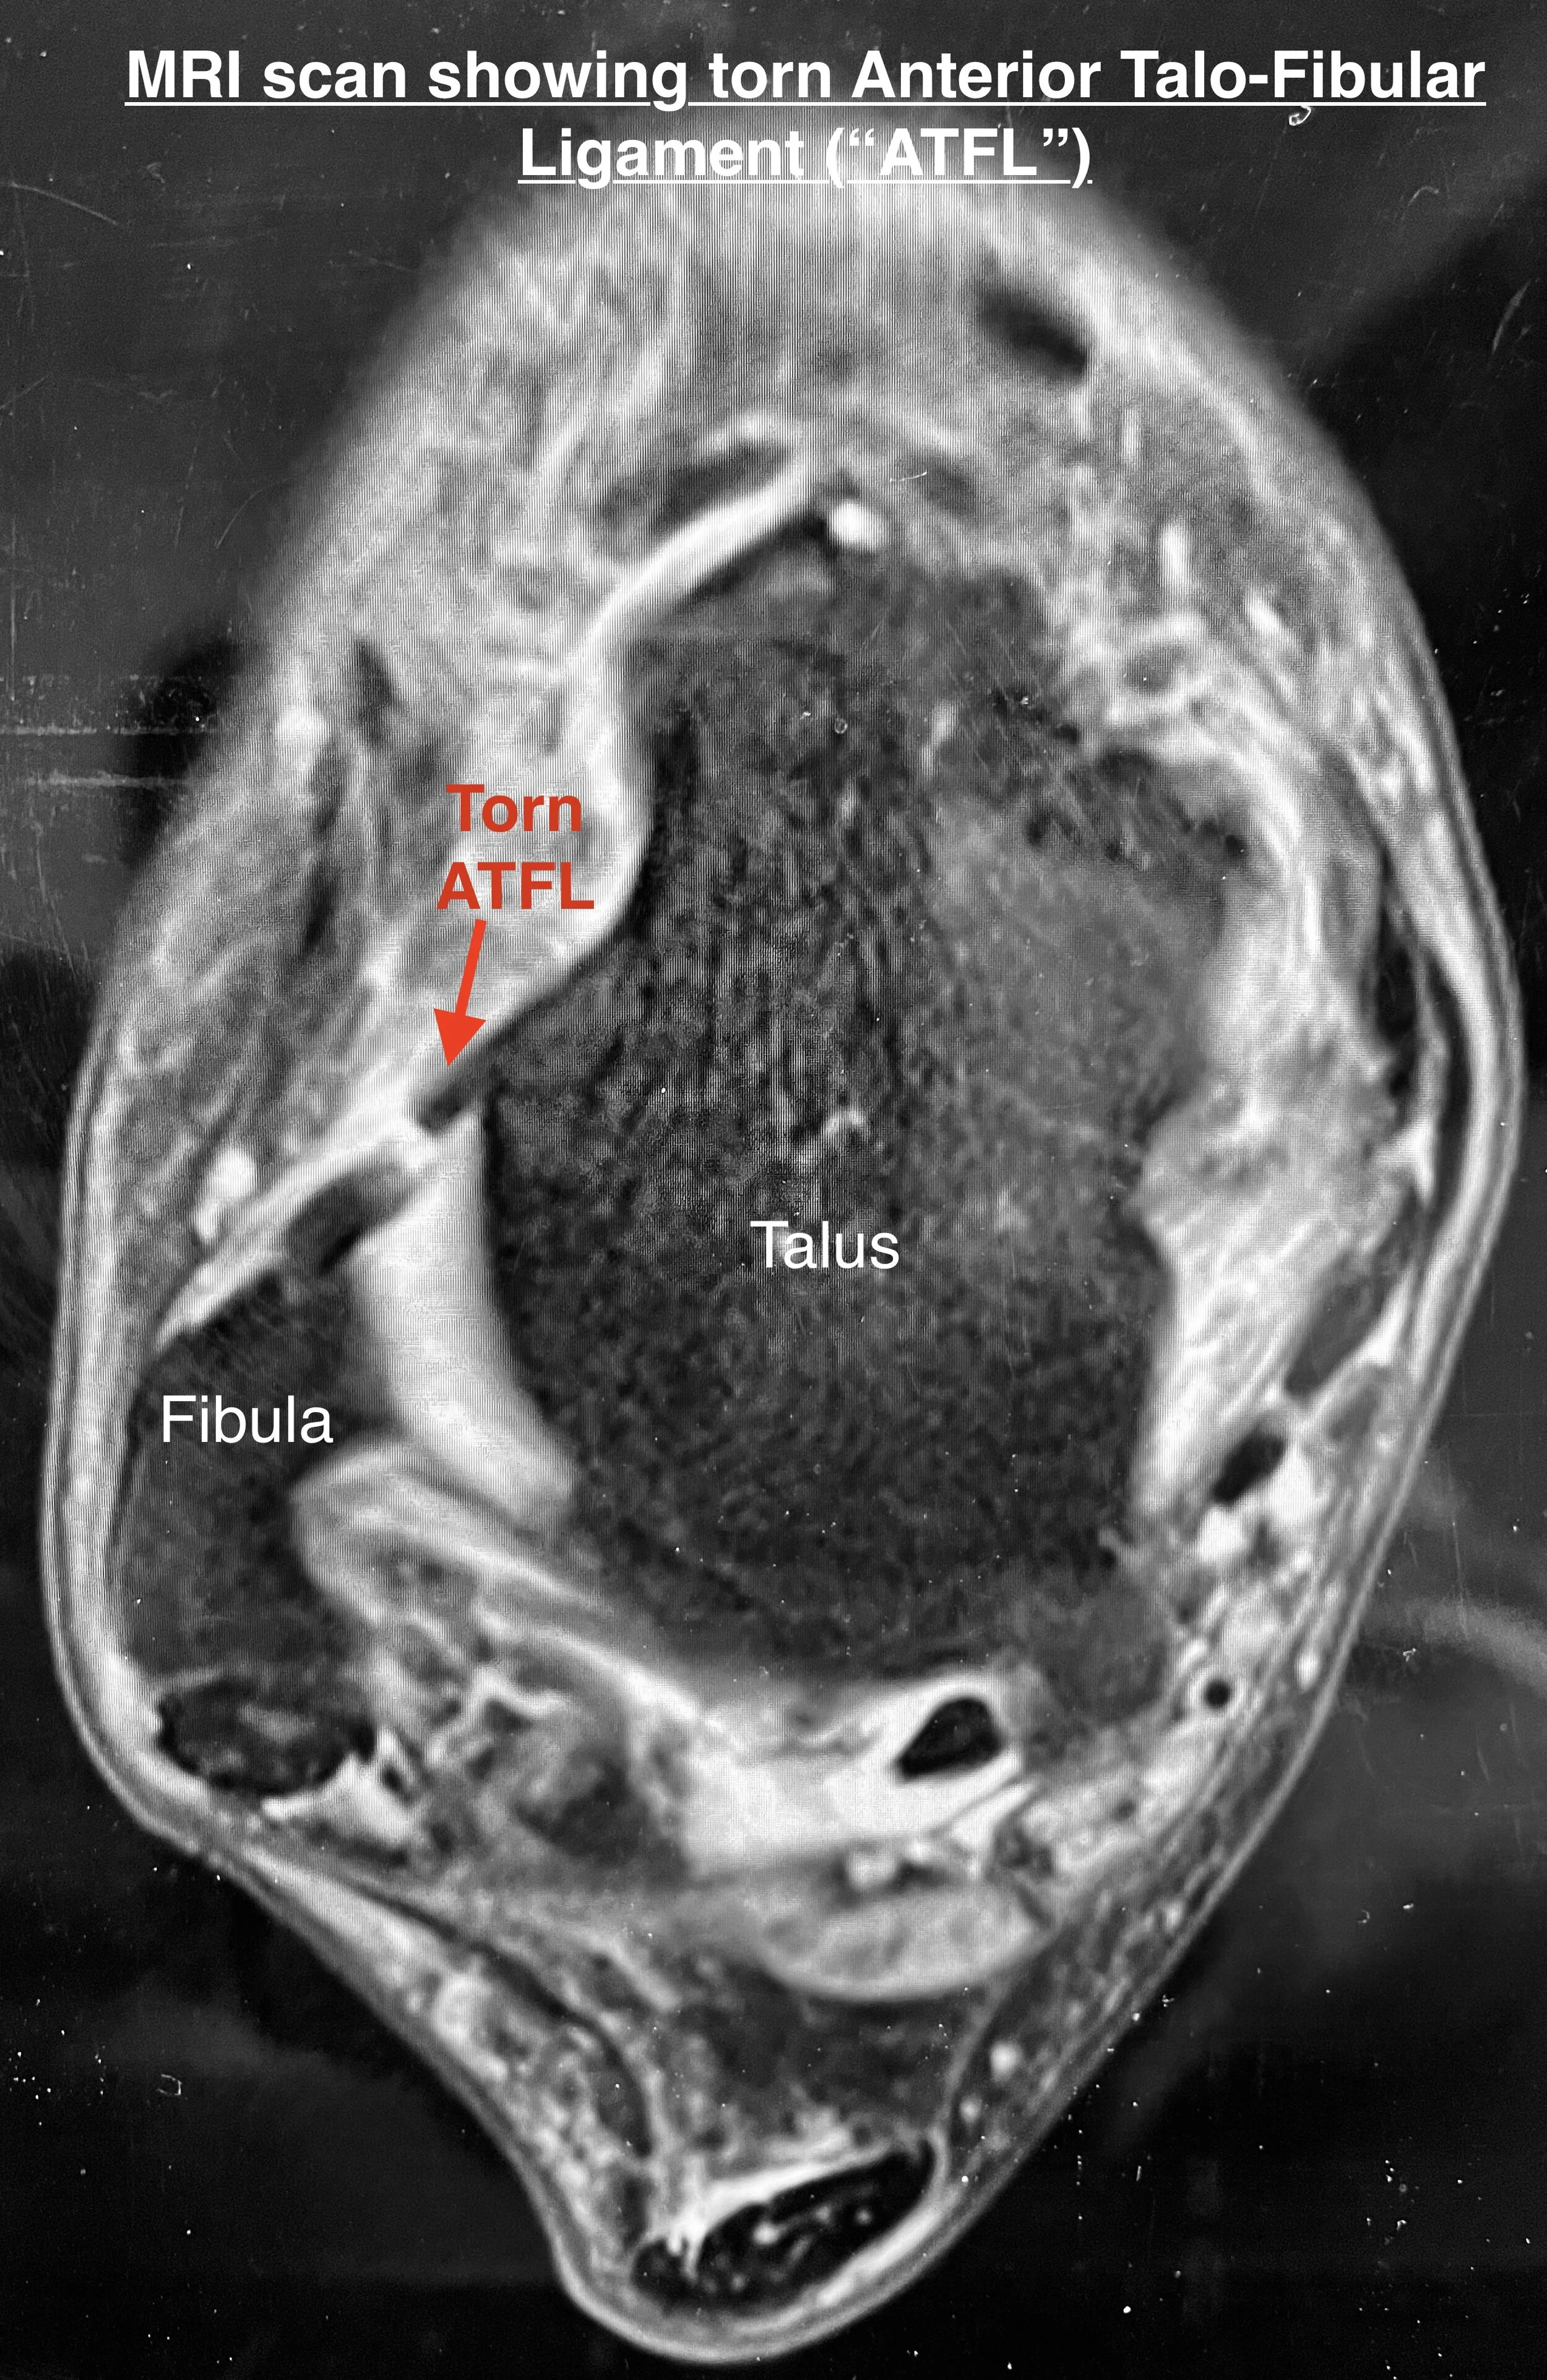

MRI scan

An MRI scan is very useful in confirming torn or damaged ligaments in the ankle and is also important to ensure that there is no other damage to the nearby tendons or the ankle joint.

This image shows a cross section of the ankle on MRI and the torn anterior talofibular ligament can be clearly seen. This is the most commonly injured of the ankle ligaments and failure of this ligament to heal properly can lead to symptoms of instability (ankle giving way or rolling over easily) and/or insecurity (not trusting the ankle).